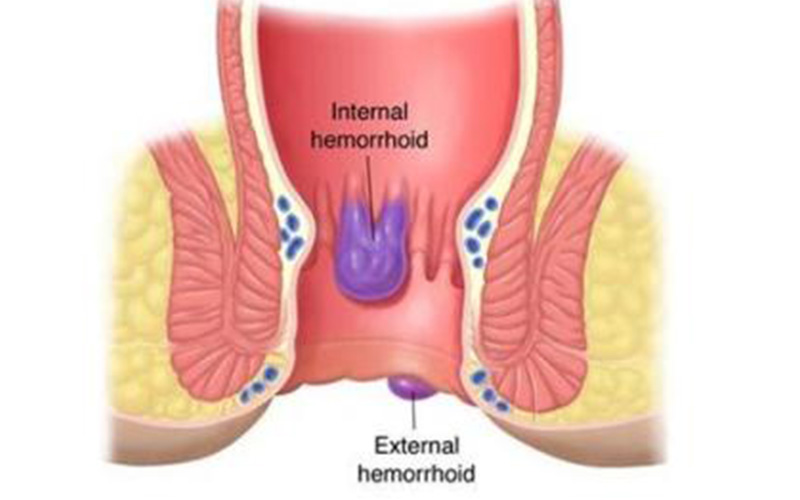

痔瘡與直腸息肉

A:直腸息肉和痔瘡都是比較常見的一類肛腸疾病,這兩者有著明顯的區別,直腸息肉形成的原因和內痔形成的原因是不同的,直腸息肉是指直腸黏膜表面向腸腔內凸起的良性病變,其發生的原因可能是由炎症所導致,也可能是由外傷所導致黏膜出現增生性改變所導致,並且直……

A:直腸息肉和痔瘡在臨床的表現上,都可以在肛門內或者是肛門外摸到質軟的腫物,按壓的時候也沒有疼痛感。大便乾燥的時候這兩種疾病均可以導致一定便血,但是直腸息肉屬於實體腫瘤,發生於直腸的黏膜層。痔瘡屬於血管內病變,它並非實質腫瘤,而是一團增多的血管……